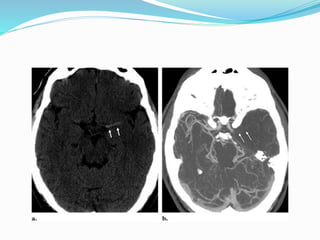

 MR angiograms in two patients with acute stroke

symptoms reveal flow gaps in the left proximal middle

cerebral artery (arrow in a) and the basilar artery (arrows

in b). Both findings were due to intravascular thrombi

MR ANGIOGRAPHY  Sensitivefor intravascular thrombus.  MR angiograms in two patients with acute stroke symptoms reveal flow gaps in the left proximal middle cerebral artery (arrow in a) and the basilar artery (arrows in b). Both findings were due to intravascular thrombi